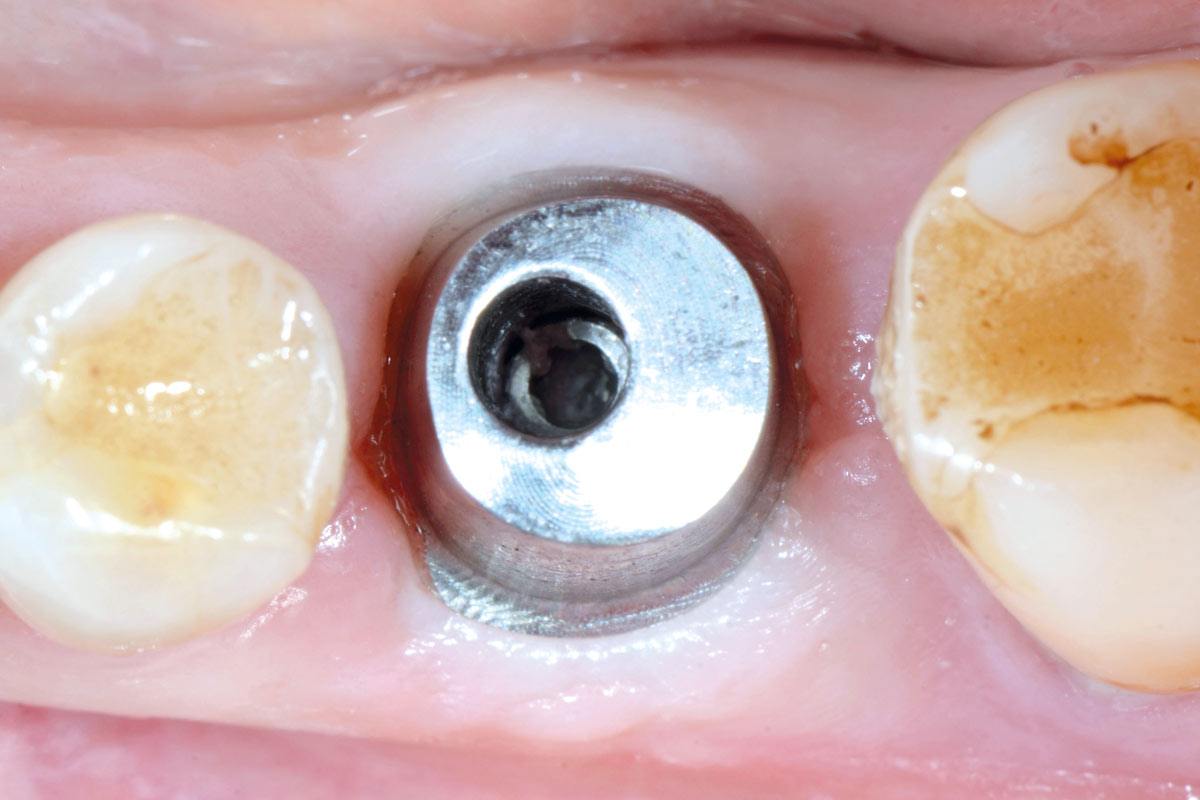

Clinical situation before extraction and implantation